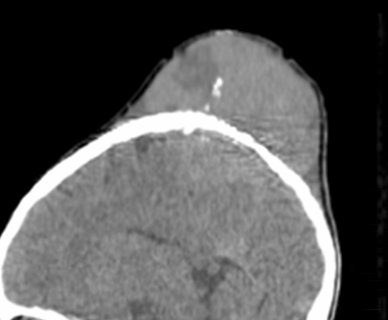

囊液

囊液主要指骨囊肿囊壁细胞分泌的液体。X 线平片表现为骨破坏区密度较低,CT 表现为水样密度(图 30),MRI 为典型的液体信号呈 T1WI 低信号和 T2WI 高信号(图 31),CT 和 MRI 增强后均无强化。

图 30.囊液:单纯性骨囊肿